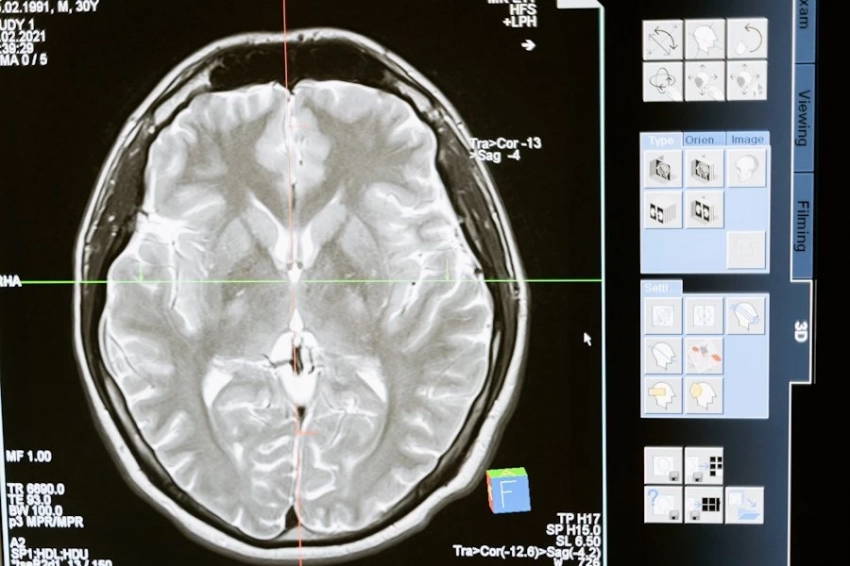

Новое исследование в Lund University (Швеция) показало, что привычка к чтению может значительно влиять на структуру мозга, особенно в областях, связанных с обработкой языка. У людей с навыками чтения обнаружены уникальные изменения в левом полушарии. Это, в частности, передняя височная доля, которая помогает связывать значения слов, и извилина Гешля, играющая ключевую роль в восприятии звуков языка.

Согласно изданию Neuroscience News, ученые отмечают, что чтение развивает толщину коры мозга в этих областях, что напрямую связано с лучшими навыками интерпретации и анализа информации. Интересно, что даже такие, на первый взгляд, «слуховые» зоны, как извилина Гешля, связаны с чтением, так как этот процесс требует фонологической обработки — способности сопоставлять буквы и звуки.

Исследование подчеркивает пластичность мозга: регулярное чтение со временем изменяет его структуру, помогая эффективнее справляться с когнитивными задачами. Однако есть и тревожные данные — всё меньше людей читают ради удовольствия. Согласно опросам, половина взрослых в Великобритании не читают книги регулярно, а среди молодежи этот показатель ещё ниже.